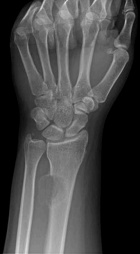

32 y/o spanish speaking female with one month of intermittent pain associated with a mass in left wrist. Pain began after playing the drums. No constitutional sx.

PE: Palpable 2cm mass dorsal distal forearm, TTP w/o crep, no LAN, erythema, edema, neurovascularly intact